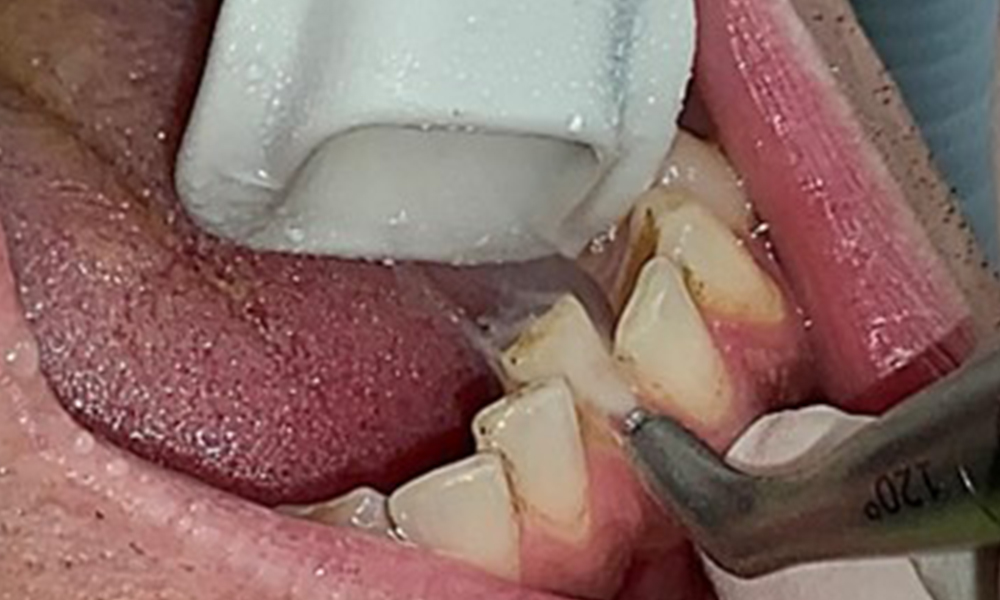

Vue rapprochée des dents

Fig. 5: Vue rapprochée des dents 45 à 47. Les flèches vertes montrent l'attrition dentaire et les érosions des cuspides buccales avec perte partielle d'émail., © Dr R. Krapf